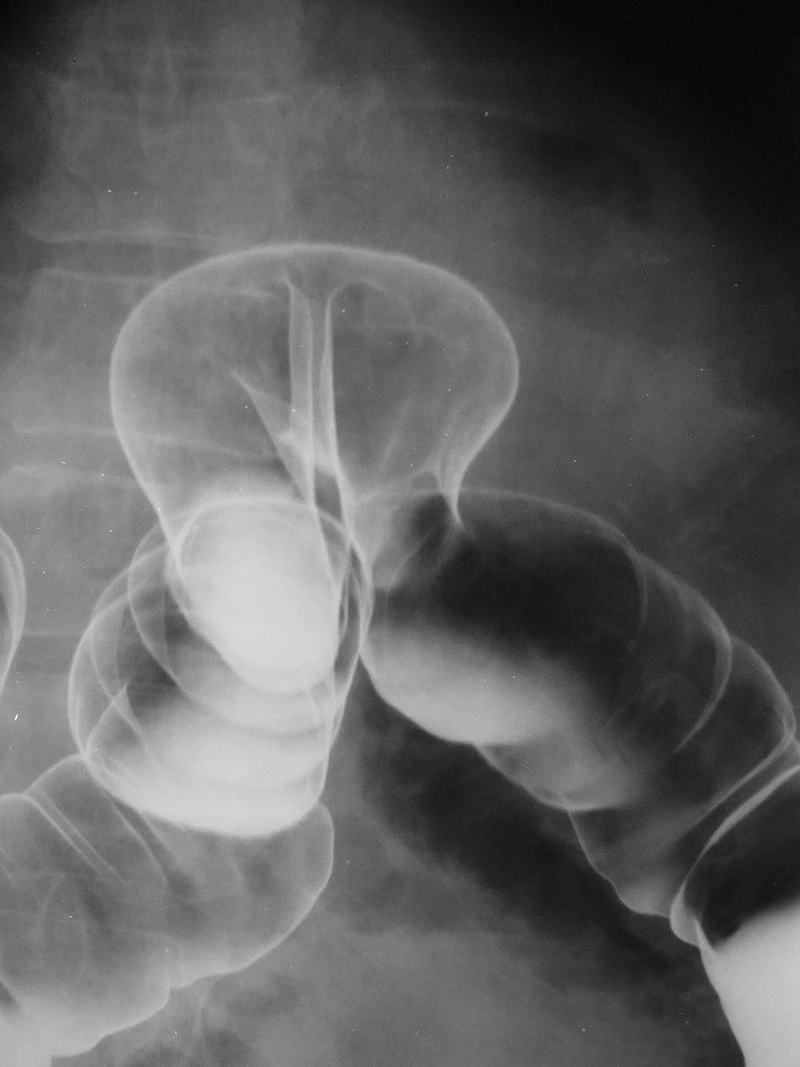

Контрастную рентгенографию верхних отделов ЖКТ врачи назначают довольно часто при таких заболеваниях, как язва, гастрит, грыжа желудка, новообразования в виде опухоли и др. При этом для контраста медики используют сульфат бария: он отражает рентгеновские лучи и позволяет получать более детальные снимки. Препарат растворяют в воде и дают пациенту выпить перед исследованием и во время него.

По утверждениям химиков, медицинский барий (0,05 (H2O)%) действительно не ядовитый. Смертельно отравиться им невозможно. При рентгеноскопии он хорошо обволакивает слизистую желудка и кишечника, позволяет врачам увидеть четкую картинку, но при этом не всасывается и через желудочно-кишечный тракт полностью выводится из организма. В отличие от медицинского технический или промышленный барий токсичен, способен всасываться в организм и отравлять его.